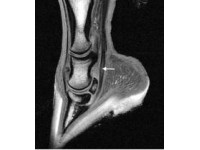

To those within the equine industry, the occurrence of a tendon or ligament injury can be very problematic. Tendons and ligaments can be distinguished by the functions they each carry out – namely, tendons connect muscle to bone whereas ligaments connect bone to bone. These tissues must have the ability to stretch (like an elastic band) in order to allow flexibility that is required for general everyday movement.